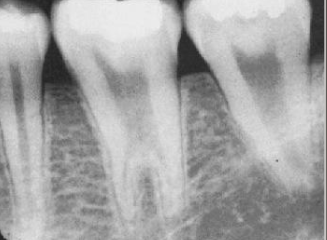

a hereditary condition of dentin in the absence of any systemic disease (opalescent dentin), AD, genetic mutation is DIFFERENT from osteogenesis imperfecta

dentinogenesis imperfects (DGI)

DGI-II clinical presentation

isolated opalescent teeth, most common

affects both dentition, steel-grey/ translucent/ opalescent crowns, brittle enamel

DGI

DGI radiographic presentation

bulbous crown, cervical constriction, pulp obliteration varies, expanded pulp = shell teeth